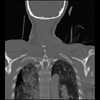

23 ANGIO,CE,Cor-MIP,5.000,ANGIO,Cor-MIP,